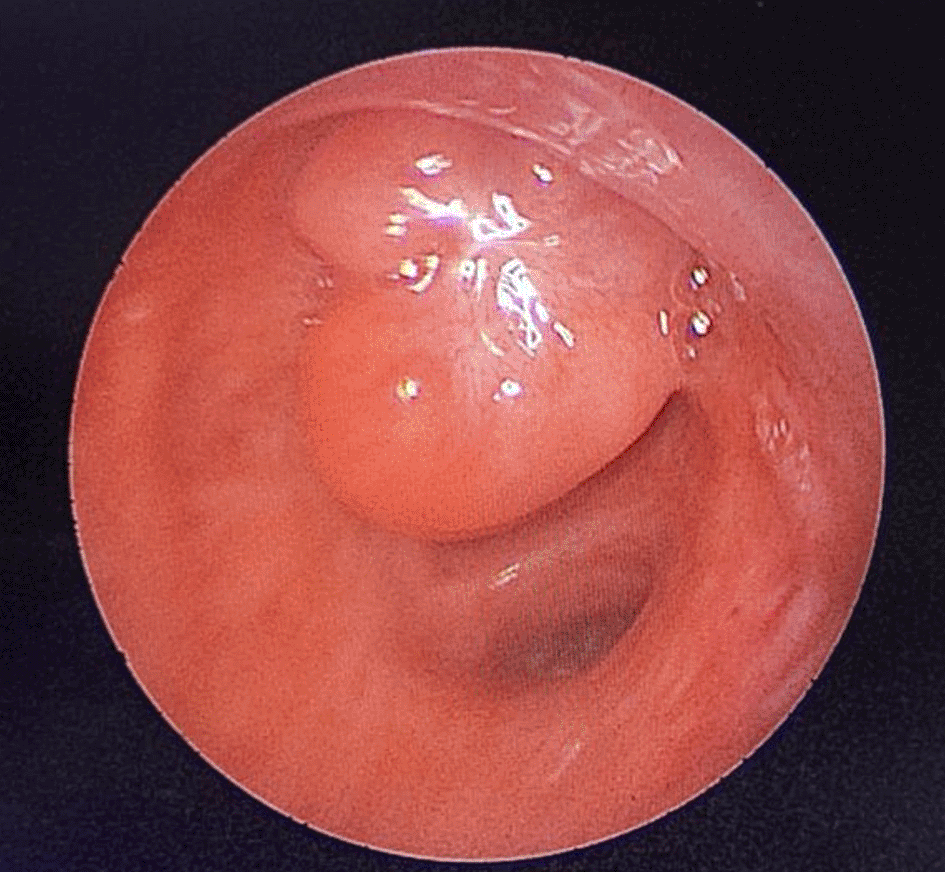

A 43-year-old nonsmoker man was referred to our department for respiratory preparation before surgical excision of an endobronchial HC. Medical history included sinonasal polyposis and diffuse bronchiectasis diagnosed at the age of 12 years with a negative etiological assessment and right lower lobectomy 4 years ago. On admission, the patient had purulent sputum with no other associated symptoms, including fever, dyspnea, or hemoptysis. Chest auscultation revealed wheezing, and the patient’s oxygen saturation level was 93% (room air). The patient was treated for a bronchial superinfection. Results of microbiological investigations were negative. Flexible bronchoscopy performed after the patient improved revealed a yellowish polylobed budding formation that completely obstructed the middle lobe bronchus (Figure 7). Chest CT-scan revealed an endobronchial lesion of fatty density in the middle lobe bronchus measuring 13 mm, responsible for minimal bronchiectasis of the middle lobe downstream, with almost total atelectasis of the latter, minimal bronchiectasis of the superior lingular segment, and sequelae of right lower lobectomy (Figure 8). After a multidisciplinary discussion and consideration of the patient’s history, endoscopic treatment was decided. Rigid bronchoscopy revealed a smooth pale pink tumor that completely occluded the middle lobe bronchus and protruded into the bronchus intermedius (Figure 9). Diode laser treatment (20 W, 620 J) was performed before mechanical ablation of the tumor using the tip of the bronchoscope. No additional instruments were required. After removal, total recanalization of the middle lobe bronchus and its subsegments without endobronchial secretions was observed. Macroscopic examination revealed 2 fragments measuring 1.5 * 1.5 cm and 0.5 cm long axis, yellowish in color and with a smooth surface (Figure 10). No complications such as bleeding, respiratory failure, or superinfection occurred. Histopathological examination of the samples stained with Hematoxylin and Eosin (H&E) showed the presence of nodules of hyaline cartilage admixed with fibrous adipose tissue, spindle cells, and myxoid stroma (Figure 11). The diagnosis of endobronchial HC was confirmed. Flexible bronchoscopy performed 2 months after patient discharge revealed recurrence of a small yellowish formation, which reduced the lumen by 50% and was completely resected with biopsy forceps. Histological examination revealed an ulcerated bronchial mucosa seat of a hyperplastic fleshy bud, without signs of specificity or malignancy. No recurrence was observed after a follow-up period of 12 months.